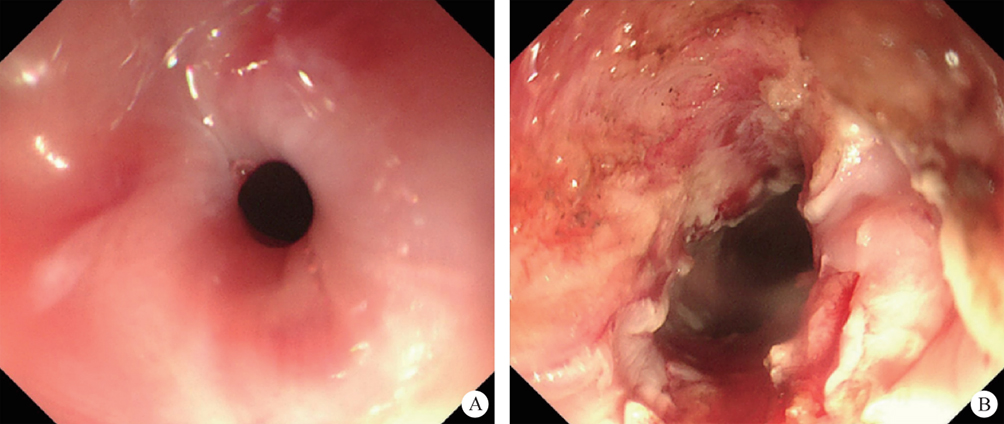

1. Classic digestive tube channel. The classic digestive tube approach refers to the path through the continuous tube from the mouth to the anus. The wall of the tube is generally divided into the mucosal layer, submucosal layer, muscularis propria layer and serous layer, from the intracavitary to the extracavitary layer. So far, most gastrointestinal endoscopy operations have carried out in this tube.

After endoscopic resection of circumferential esophageal lesions, almost 100% of patients experienced symptoms like esophageal stenosis and an inability to eat. Our team is the first in the world to carry out endoscopic autologous skin flap transplantation to prevent stenosis after endoscopic resection of esophageal circumferential lesions (figure 2.1), and 19 cases of autologous transplantation of skin flaps and simple placement of an esophageal stent for the prevention of esophageal stenosis were compared. The results showed that rate of stent removal for the group who had received an autologous skin flap transplantation was significantly reduced compared to the group with a simple esophageal stent (36.8%–78.9%). Currently, this research is also aimed at optimizing surgical and transplant methods, so as to improve the survival rate of skin flaps and to reduce the rate of occurrence of esophageal stenosis.